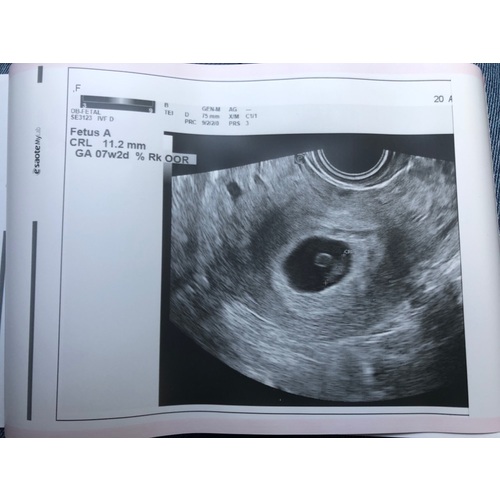

Dit is de mijne 馃槈

Ook jongen xxx Kim